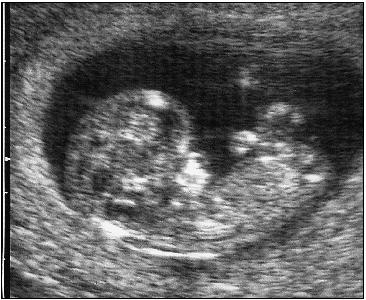

«Ἡ ἐπιστημονικὴ πρόοδος στὸν τομέα τῆς Ἐμβρυολογίας, ἀλλὰ καὶ ἡ τρισδιάστατη εἰκόνα τῶν ὑπερήχων πιστοποιοῦν τὴν ἀπὸ αἰῶνες διδασκαλία τῆς Ἐκκλησίας μας ὅτι ἡ ἀνθρώπινη ζωὴ ἀρχίζει «ἐξ ἄκρας συλλήψεως», δηλαδὴ τὴ στιγμὴ ποὺ τὰ 23 χρωμοσώματα τοῦ ὠαρίου ἑνώνονται μὲ τὰ 23 χρωμοσώματα τοῦ σπερματοζωαρίου καὶ δημιουργεῖται τὸ πρῶτο κύτταρο, τὸ ζυγωτό. Συγχρόνως, ὅμως, τότε σφραγίζεται καὶ ἡ προσωπικότητα τοῦ κάθε ἀνθρώπου, μὲ τὸ πλῆθος τῶν γονιδίων ποὺ παραλαμβάνει ἀπὸ τοὺς γονεῖς του.

Πρόσωπο μοναδικὸ καὶ ἀνεπανάληπτο θεωρεῖται τὸ ἔμβρυο καὶ ὡς τέτοιο ἀναγνωρίζεται παγκοσμίως. Ὡς «πρόσωπο» τὸ ἀναγνωρίζει καὶ τὸ Δίκαιο τῆς πατρίδας μας καὶ τὸ καθιστᾶ ὑποκείμενο καὶ φορέα ἀστικῶν δικαιωμάτων, π.χ. τὸ ἄρθρο 1711 τοῦ Ἀστικοῦ Κώδικα, σύμφωνα μὲ τὸ ὁποῖο τὸ συλληφθὲν ἔμβρυο μπορεῖ νὰ κληρονομήσει περιουσιακὰ στοιχεῖα συγγενῶν του, ἐὰν γεννηθεῖ ζωντανό.